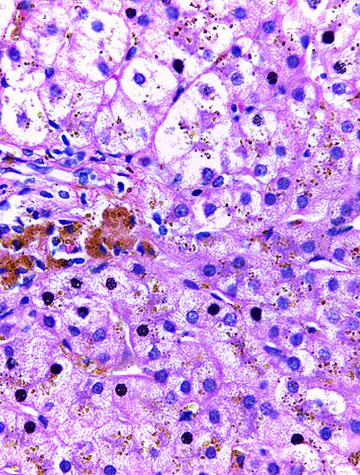

La sarcoïdose est une maladie multi-organique de cause inconnue caractérisée par une inflammation granulomateuse non nécrosante, touchant le plus souvent les poumons. La confirmation nécessite d’exclure d'autres affections, dont la bérylliose chronique qui ne peut être distinguée de la sarcoïdose sans tests spécifiques. Si la bérylliose chronique se développe principalement après inhalation de béryllium, la sensibilisation cutanée constitue un risque, et surtout, une [...]